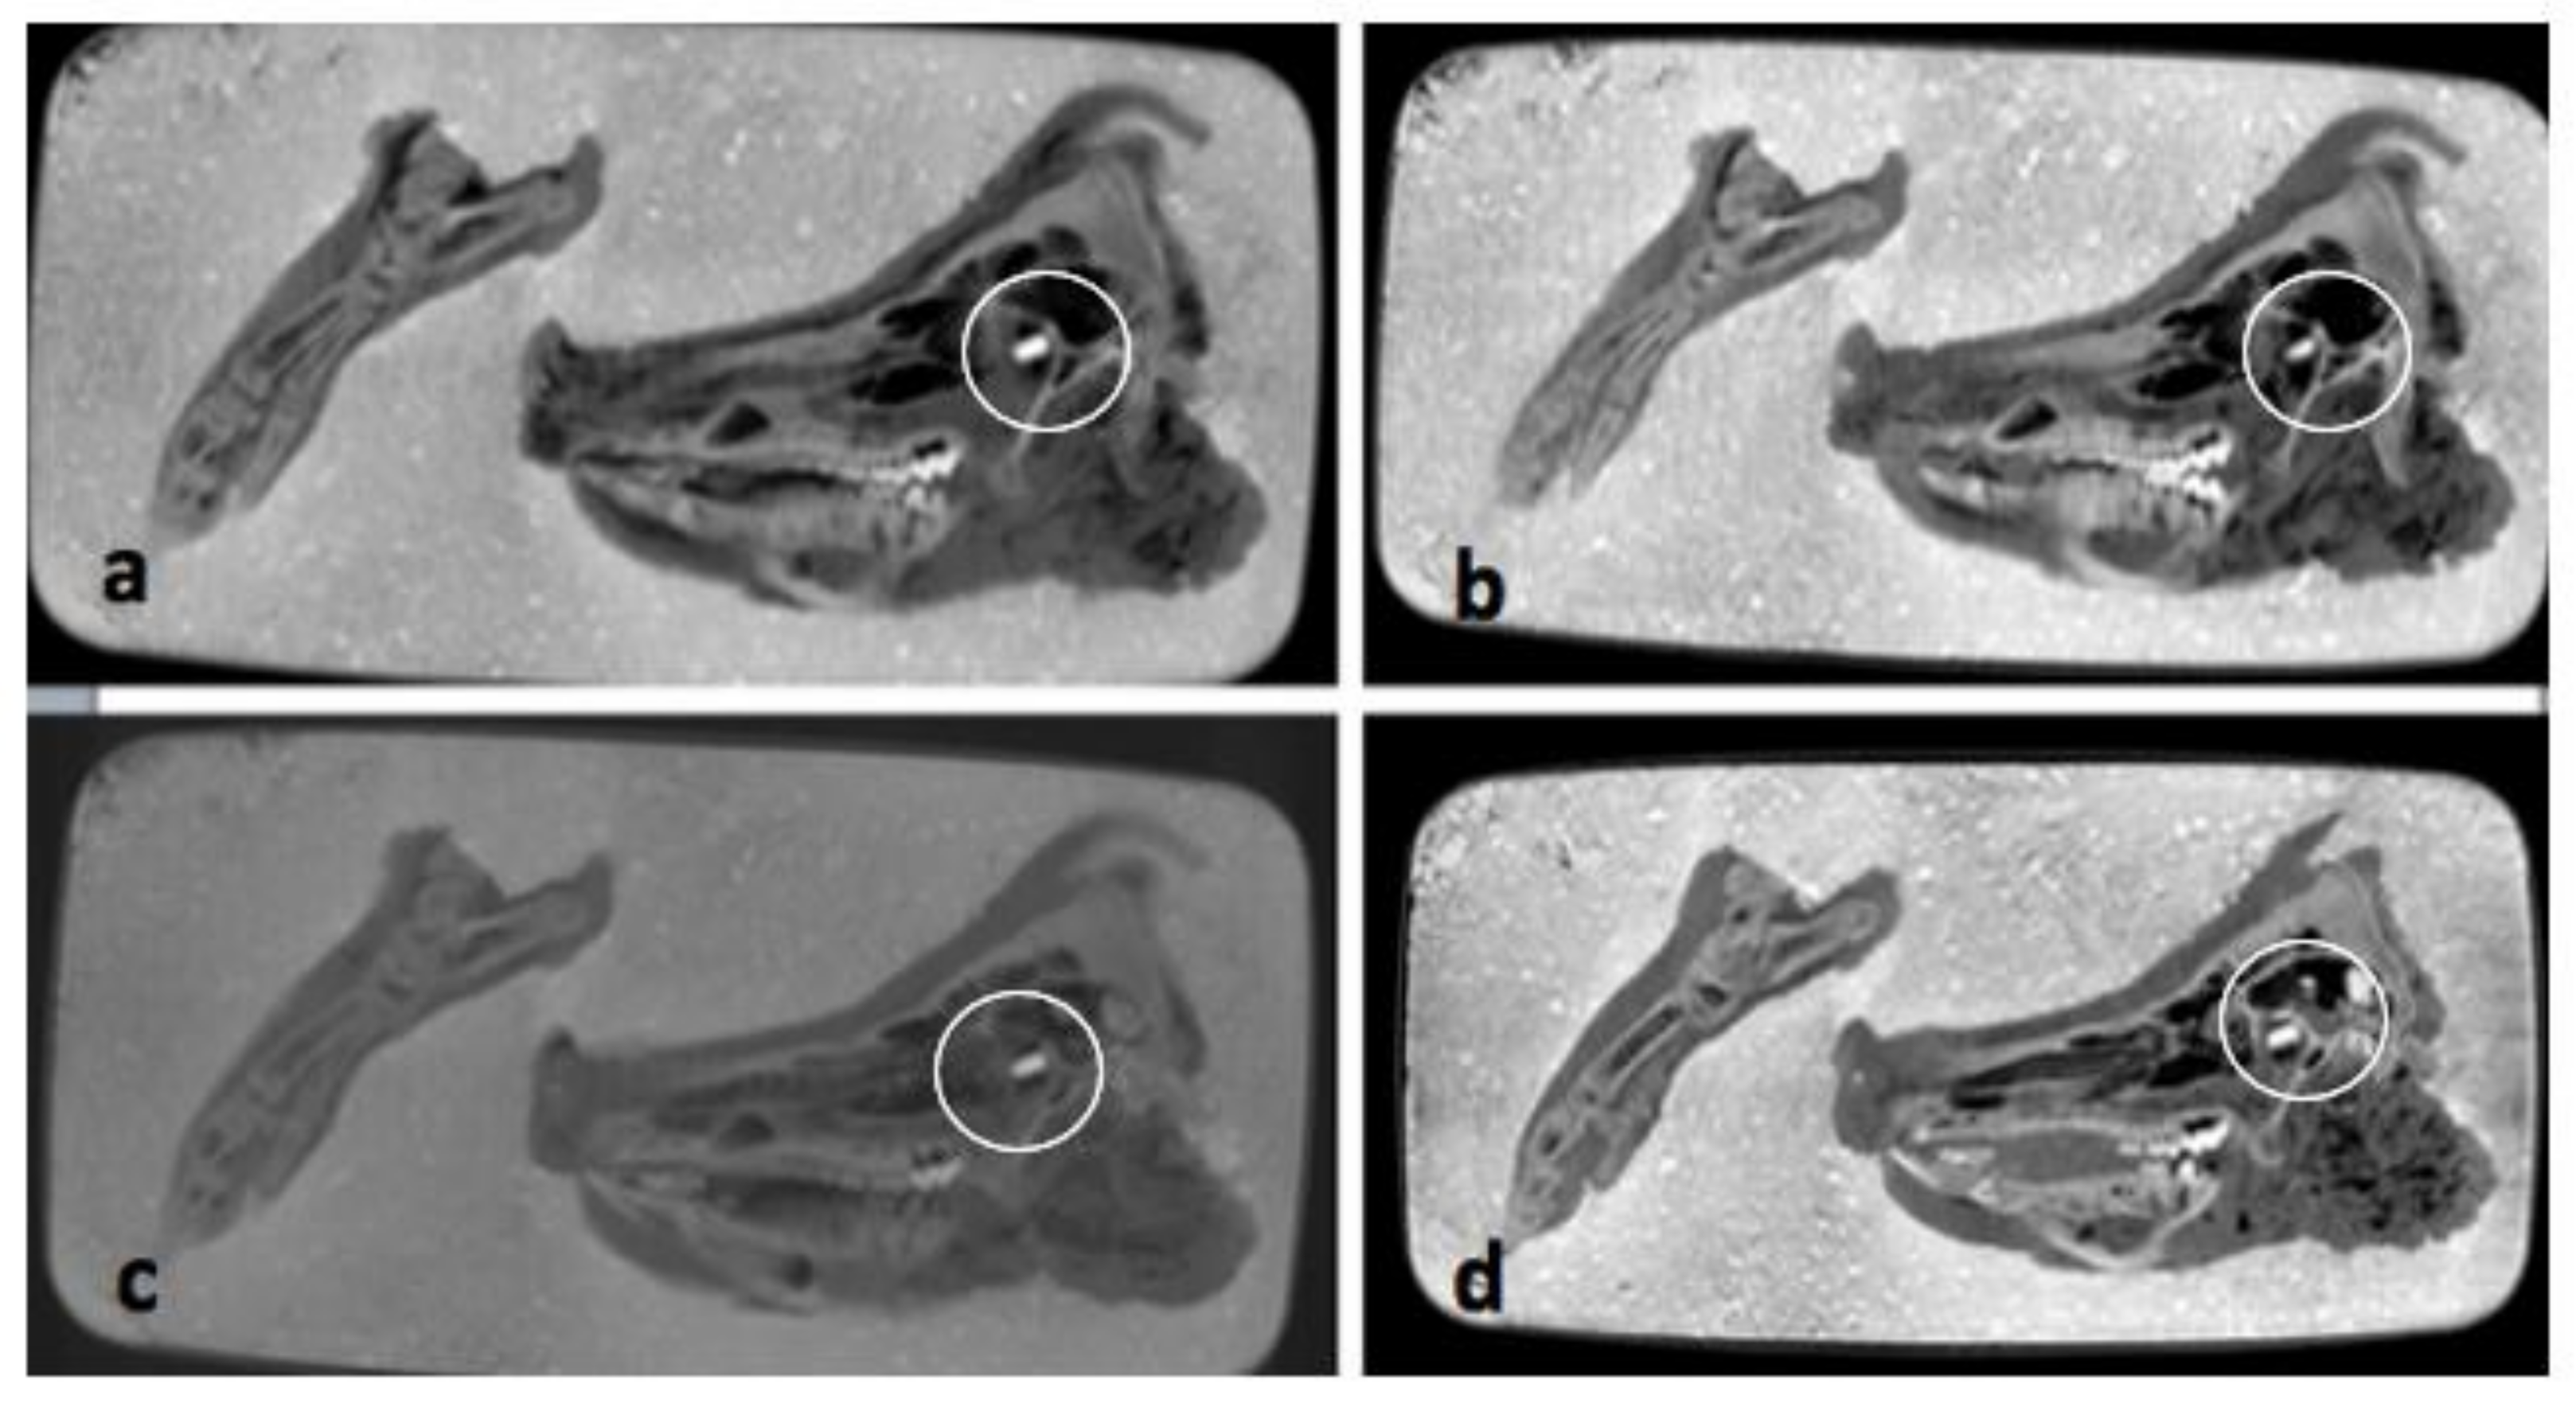

The pmCT scans in the axial plane (see Figure 4a–d), do not show any relevant changes over the course of one year. The bones and soft tissues are clearly visible on each scan, as is the projectile inside the orbit. The thickness and shape of soft tissues covering the bones remained almost unchanged over time. The amount of air inside the sinuses and soft tissues fluctuated, but there is no clear direction over time.

Figure 4.

(a–d) Comparisons of pmCT images in axial plane from 30 September 2020 (a), 21 December 2020 (b), 3 March 2021 (c) and 25 August 2021 (d). The projectile is marked with a circle in all four images.

On the exemplified radiographs in Figure 5a–d, a darkening can be seen covering the pig’s head and paw and progressing over time. This could be an indirect sign of decomposition of the soft tissues. The outline and the projectile in the eye socket of the pig are clearly visible in each image. The projectile can be seen in black due to the high combined density of the metal and the surrounding concrete.

Figure 5.

(a–d) Comparisons of X-ray images from 30 September 2020 (a), 21 December 2020 (b), 3 March 2021 (c) and 25 August 2021 (d). The darkening is shown by arrows. The projectile is marked with a circle in all four images. Quality of the images is due to the reduced radiation density in the portable X-ray machine.